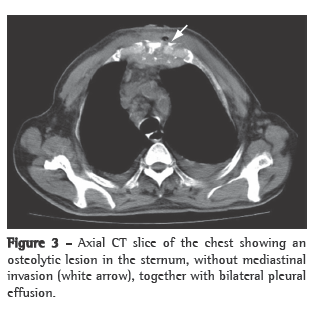

Treatment with ciprofloxacin and clindamycin was initiated. The blood workup revealed normochromic normocytic anemia, the PPD test was positive (induration = 15 mm), HIV testing (ELISA) was negative, and erythrocyte sedimentation rate (ESR) was 48 mm/h. Imaging studies (anterior and lateral chest X-rays) revealed no pleuropulmonary findings suggestive of previous or active TB. A lateral X-ray of the sternum revealed an osteolytic lesion in the region of the suprasternal notch and the first costal arches (Figure 2). A CT scan of the chest revealed an osteolytic lesion in the suprasternal notch, without mediastinal invasion, as well as bilateral transudative pleural effusion related to the clinical profile of pulmonary hypertension and decompensated heart failure (Figure 3). In addition, technetium triphasic scintigraphy showed no increased radiotracer uptake in the lesion. The swab specimen revealed Gram-positive cocci in pairs, and culture was positive for multidrug-resistant Staphylococcus aureus and negative for fungi and mycobacteria after 70 days of incubation. The antibiotic regimen was changed to oxacillin. The result of the histopathological examination of the sternal lesion revealed caseous granuloma. For PCR analysis (Álvaro Laboratory, Cascavel, Brazil), a second sternal biopsy was performed, and the empirical treatment for TB using regimen I (rifampin, isoniazid and pyrazinamide) was initiated. The patient presented a favorable response. The PCR analysis was positive for Mycobacterium tuberculosis, confirming the diagnosis of tuberculous sternal osteomyelitis.

From a radiological standpoint, sternal TB can present the following patterns of bone destruction: osteolytic lesions; periosteal reaction; enhancement patterns; and soft tissue abscess with or without internal calcium formations.(6) These findings, which are not exclusive to sternal TB, can be found in aggressive infections such as actinomycosis.(8)

Although CT does not appear to have any advantage over sternum X-ray in the evaluation of bone involvement, it is significantly superior in the evaluation of perilesional soft tissues, mediastinal involvement and pulmonary involvement.(5-9) Magnetic resonance imaging is a good option for the evaluation of soft tissues and bone lesions, revealing early alterations in the bone marrow, especially at early stages with normal X-ray findings.(4,5,9) Technetium triphasic scintigraphy has high sensitivity and specificity for the diagnosis of osteomyelitis.(2,4) In the case presented here, there was no increased radiotracer uptake in the sternum or photopenia in the osteolytic lesion, nor were there any other findings consistent with osteomyelitis.